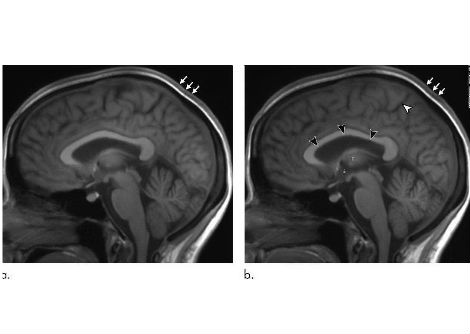

وُصف فيروس CMNV في الأصل بوصفه فيروساً عقدياً مسؤولاً عن مرض الوفيات الخفية في روبيان المزارع المائية (Penaeus vannamei)، ويتميز بإحداثه نفوقاً جماعياً دون أعراض سريرية خارجية واضحة. ينتمي إلى عائلة الفيروسات ذات الحمض النووي الريبي أحادي الشريط موجب الاتجاه، ويمتاز بقدرته على إصابة أعداد واسعة من المضيفين في البيئات المائية. وقبل هذا التقرير، وثّقت دراسات سابقة قدرة الفيروس على إصابة أسماك غوبي (Mugilogobius abei) بصورة طبيعية، مُحدِثاً آفات شبكية وتغيرات نسيجية مرضية عينية، فضلاً عن إثبات إصابته التجريبية لأسماك الزيبرافيش (Danio rerio) مع أمراض عينية مشابهة. وتجدر الإشارة إلى أن المستضد الفيروسي رُصد أيضاً داخل أنسجة العين وعنيقها في الجمبري المصاب. يُشير هذا التوجه الثابت نحو البنى العينية عبر أنواع مضيفة متباعدة تطورياً — من اللافقاريات إلى الأسماك الفقارية — إلى تقارب بيولوجي حقيقي للفيروس مع الأنسجة العينية، لا إلى انتشار عرضي.

ضمّت المجموعة السريرية 70 مريضاً مصابين بمتلازمة POH-VAU، أُثبتت لديهم التحولات المصلية (Seroconversion) تجاه CMNV. يُعرَّف التحول المصلي بظهور أجسام مضادة نوعية ضد الفيروس في مصل الدم، مما يدل على عدوى نشطة أو حديثة. والأهم من ذلك، أنه جرى الكشف عن المادة الجينومية للفيروس مباشرةً داخل الأنسجة العينية، مما يُثبت أن الفيروس لم يكتفِ بالدوران في مجرى الدم، بل تكاثر بفاعلية داخل العين. عانى المرضى المصابون من نوبات متكررة من التهاب العنبية الأمامي مع ارتفاع ضغط عيني عصيٍّ على العلاجات التقليدية، مما يُشير إلى آلية التهابية مزمنة ذات منشأ فيروسي. ويُثير هذا الاكتشاف احتمال أن تكون بعض حالات الزرق الالتهابي غير المُفسَّرة أو المقاوم للعلاج ناجمةً عن مسببات فيروسية لم تُكشَف بعد.